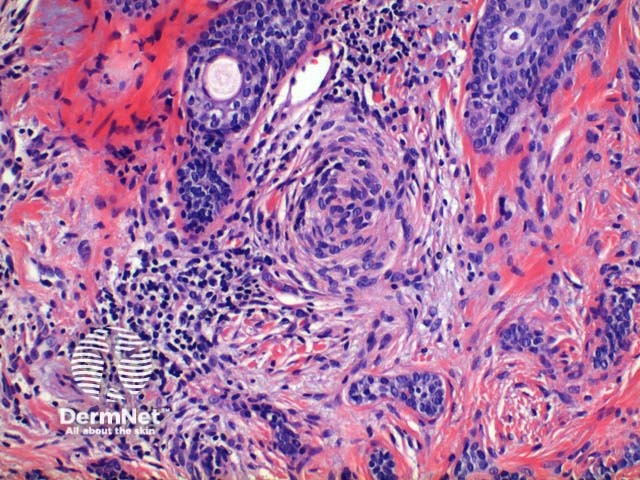

Desmoplastic trichoepithelioma: Scanning power view demonstrates an infiltrating tumour which appears to be arising from the epidermis (Figures 4, 5). The tumour is comprised of small islands of basaloid epithelium superficially which form cords and strands towards the base and periphery (Figures 6, 7). Horn cysts, frequently many, calcification and foreign body granulomas can be seen (Figures 6, 7). The cells are bland and mitotic activity is usually very low, however the infiltrative sclerosing growth pattern can cause difficulty in discriminating this lesion from syringoma or sometimes microcystic adnexal carcinoma (figure 8). Trichoblastoma is a deeper form of trichoepithelioma.